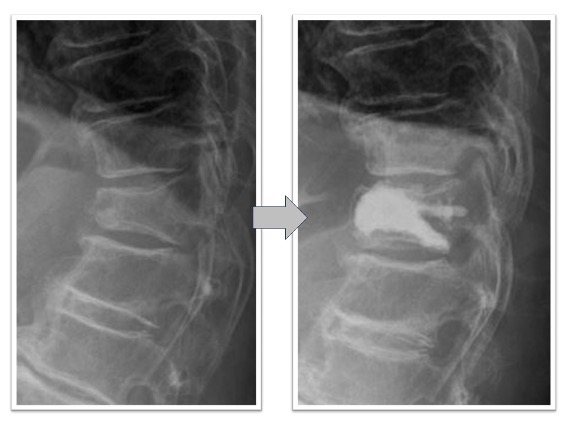

変性側弯を伴う多椎間の椎間板ヘルニア、脊柱管狭窄症(図3,4)

下肢痛、歩行障害、腰痛で来院、手術となりました。術前後のレントゲンで3椎間のOLIFによって術後側弯症が改善され、脊椎の並び(アライメント)が矯正されています(図3)。また、術前後のMRIでは施術した部位の椎間板ヘルニアおよび脊柱管狭窄がOLIFの間接除圧効果によって改善し、神経への圧迫が解除されています(図4)。術後は歩行可能、下肢痛腰痛も改善、また結果として数センチ身長が回復しています。

図3

図4